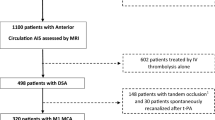

Out of the 249 participants enrolled from October 2016 to October 2022, 101 (40.6%) participants were included. One hundred forty-eight subjects were excluded due to unavailable admission DSC-MRI (n = 92) and poor-quality pre-thrombectomy DSA (n = 56). The study flowchart is provided in Fig. 1.

The study population comprised 53 (52.5%) males, with a median age of 72.0 years (IQR: [58.0, 85.0]). Upon admission, the initial NIHSS score averaged 14.5 (IQR: [8.0, 19.0]). The median volume of the infarct core volume was 17.5 mL (IQR: [6.9, 43.3]). The median time from symptoms onset to MRI was 95.0 min (IQR: [76.0, 126.0]). In the whole study population, the median ASITN/SIR score was 3.0 (IQR: [2.0, 3.0]) and the median change in K2 was 152.7% (IQR: [53.8, 427.5]). In 81/101 (80.2%) patients achieving successful thrombectomy, recanalization was considered futile in 25/81 (30.9%).